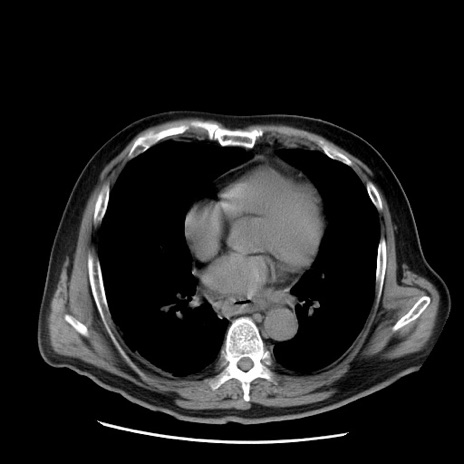

症例20(横断像)

【症例】 60歳代男性

【主訴】 腹部膨満、嘔吐

【現病歴】5日前頃より倦怠感を認め食事量減少し4日前の朝嘔吐、食事摂取困難となった。 3日前近医受診し点滴施行され整腸剤などを処方された。 当日他院を受診し、腹部膨満著明、炎症反応の上昇(CRP10.8、WBC11200)あり、紹介受診となる。

【身体所見】 意識JCS1 受け答えがはっきりしないBP 111/57mHg、 P 67bpm、、BT35.2°C、SpO2 97%(RA)、 腹部:膨隆、打診で鼓音あり、全体的に圧痛有り、腸蠕動音(-)、反跳痛ははっきりせず。

【データ】WBC 11400、CRP 14.20